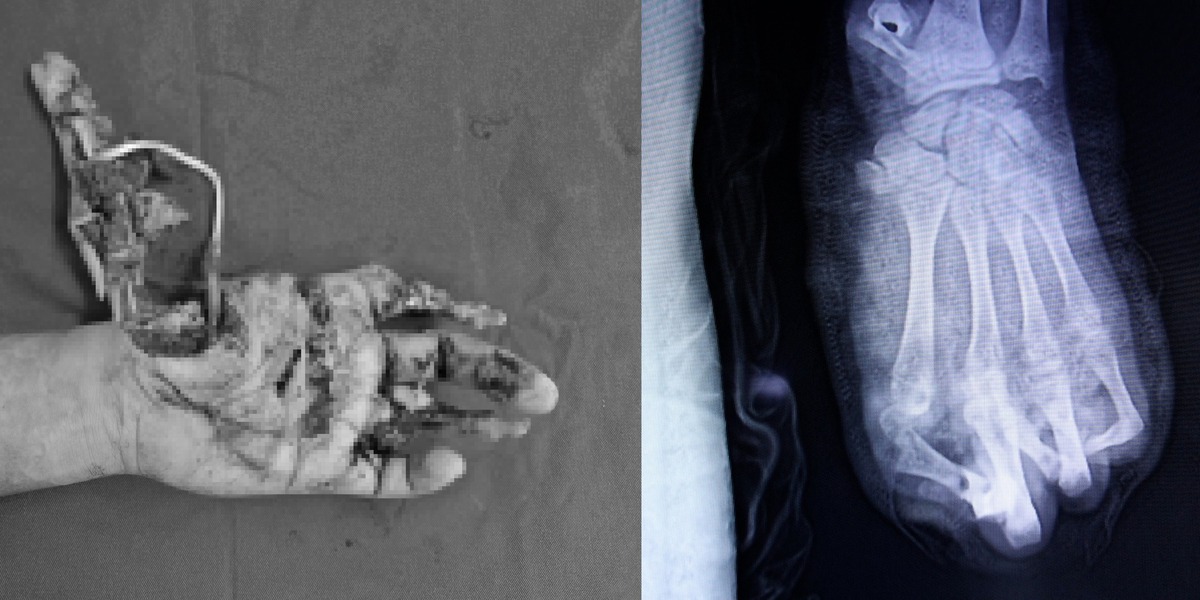

Ngày 17/1, Khoa Phẫu thuật Chi trên và Vi phẫu, Bệnh viện Trung ương Quân đội 108 (Hà Nội) tiếp nhận một nam sinh 15 tuổi trong tình trạng bàn tay trái dập nát nghiêm trọng sau khi pháo tự chế phát nổ khi em thử nghiệm tại nhà. Gia đình cho biết trước đó em xem các video hướng dẫn chế pháo trên mạng xã hội, tự đặt mua nguyên liệu rồi làm theo.

TS.BS Nguyễn Quang Vịnh – Chủ nhiệm Khoa Phẫu thuật Chi trên và Vi phẫu, cho biết tổn thương do pháo nổ là dạng chấn thương năng lượng cao. Lực nổ phá hủy diện rộng mô mềm, xương bàn tay vỡ vụn, nhiều ngón không thể bảo tồn. Ê-kíp buộc phải cắt lọc tổn thương, chỉ giữ lại hai ngón, đồng thời xử lý tổn thương mạch máu và thần kinh. Quá trình điều trị kéo dài, chức năng bàn tay bị ảnh hưởng lâu dài.

Hình ảnh chụp cánh tay của nam sinh chế pháo bị tai nạn điều trị tại Bệnh viện 108

Giữa tháng 1/2026, Trung tâm Chấn thương – Chỉnh hình – Bỏng, Bệnh viện Đa khoa tỉnh Khánh Hòa cũng tiếp nhận học sinh Đ.A.T. (15 tuổi) trong tình trạng dập nát bàn tay trái, bỏng sâu do tự chế pháo tại nhà. Các bác sĩ buộc phải tạo hình mỏm cụt để bảo tồn phần chi thể còn lại.